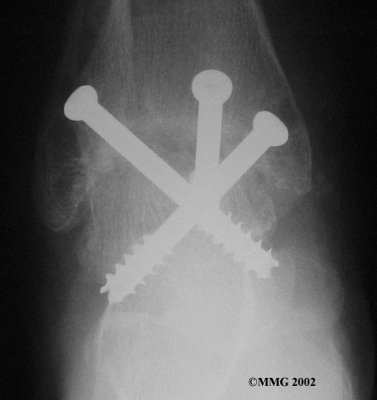

It is important when the surfaces are removed that the angles of the cut surfaces are correct. When the tibia is brought against the talus, the foot should be at a right angle to the lower leg. Once the cuts are made the bones must be held in place while they fuse. This can be done using large metal screws and metal plates if necessary. The screws are usually under the skin and are not removed unless they begin to rub and cause pain.

Inserting the screws

After ankle fusion, the physical therapists at FYZICAL Hendersonville can help you learn to walk smoothly and without a limp. Although time needed for recovery varies among patients, an ankle brace will typically replace your cast after eight to 12 weeks. Your surgeon will take X-rays frequently to see if the bones are fusing together. You will probably need to use crutches during the time you wear the cast. As the fusion grows stronger, you will begin to put more weight on your foot when walking.